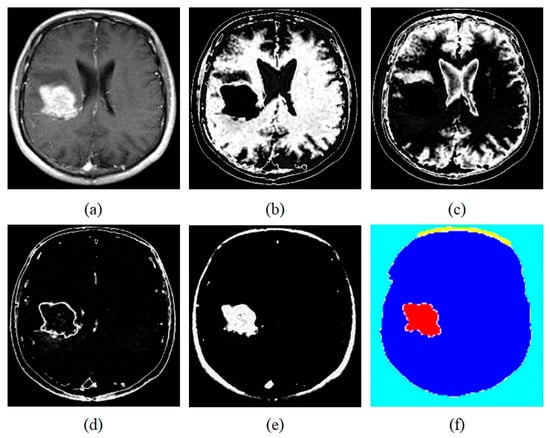

In the first part of the experiment, we assess the performance metrics of the proposed transfer learning-based DCNN model on the Figshare dataset with regards to accuracy, sensitivity, precision, and specificity. Table 2 shows the performance measures of the proposed transfer learning-based classification model. It is noticed that the proposed classification model has shown the highest percentage for four important classification measures when evaluated on the Figshare dataset. As seen, our classification framework reached an accuracy, sensitivity, specificity, and precision of 98.93%, 98.68%, 99.13%, and 99.11%, respectively. Also, we present the accuracy of each class of tumors as well as mean accuracy in Table 3. In our experiment, we have used 106 brain MRI slices having Meningioma tumor, 214 brain MRI slices having Glioma tumor, 139 brain MRI slices having Pituitary tumor for testing the proposed classification framework. As observed from Table 2, we obtain the classification accuracy for Meningioma 97.88%, for Glioma 99.29%, and Pituitary 98.38%. Finally, we have taken the mean accuracy of three classes of tumors, and it resulted as 98.51%. Table 4 illustrates the MSE loss after each convolutional layer of the proposed transfer learning-based DCNN model being trained. In addition, we present the sample experimental results obtained by the proposed framework in Figure 5. Figure 4 shows the original brain MR image with tumor image, white matter, segmented Image, gray matter, skull-stripped image, and extracted tumor respectively. The confusion matrix of the proposed transfer learning-based DCNN model is illustrated in Figure 6.

Figure 5. Tumors Detection Results using Proposed Framework (a) Original brain MR Image with tumor (b) White matter (c) Segmented Image (d) Gray matter (e) Skull-stripped image (f) Extracted Tumor.